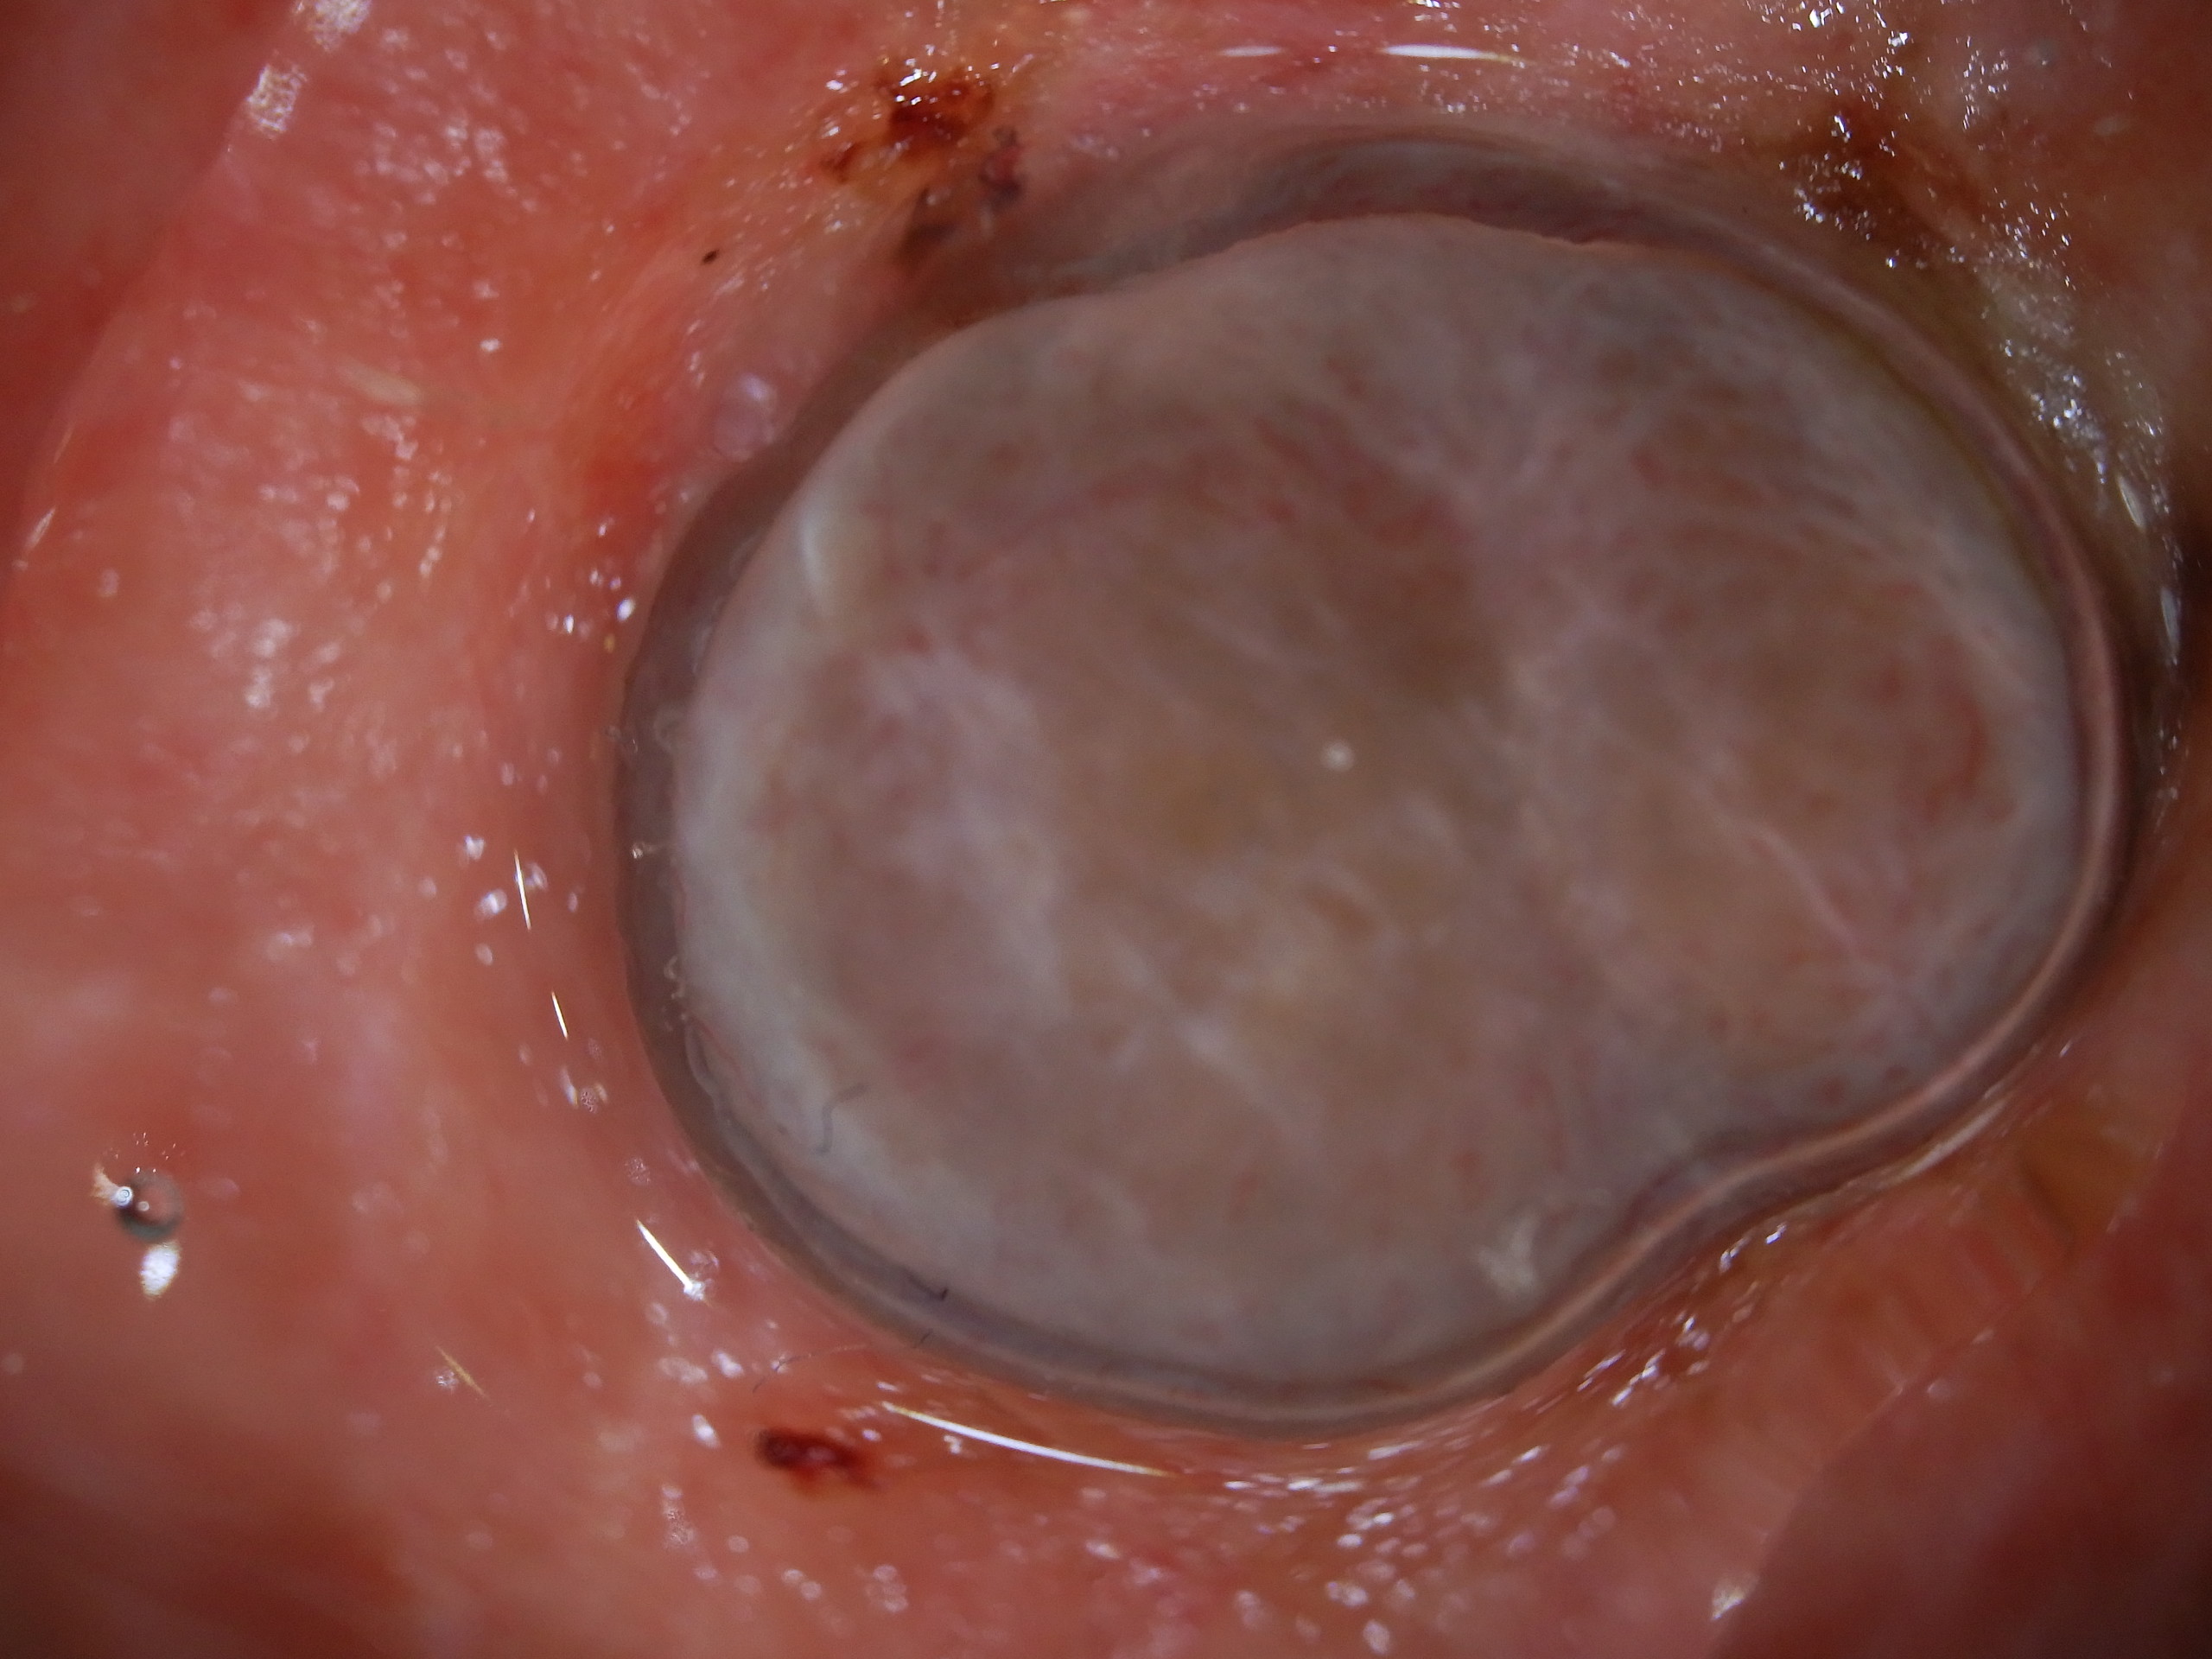

Site: Shins

Diagnosis: Melanoma nodular

Type: Dermlite Polarised

Submitted By: Ian McColl

Description: Blue grey nodule on the shin

Past history of several melanomas including a blue nevus like melanoma metastasis. Rapid growth over 6 weeks of this blue grey nodule on the shin. No local glands in groin. This was a 6 mm thick pigmented nodular melanoma. Compare it with the previous case.